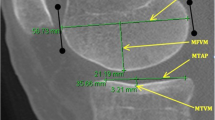

MRI images were obtained using 1.5 T (GE SIGMA LX, Milwaukee, USA) scanner and volume architecture design receive coil. The fast spin echo (FSE) sequence T1 was acquired in both axial and sagittal plane and used for image analysis. Measurements were taken through sets of 1 mm spacing slices and made by the same independent experienced musculoskeletal radiologist. The measurements (in mm) were calculated by the distance from two perpendicular lines to the tibial slope, crossing the most posterior points of the tibial plateau and the femoral condyle. Objective criteria for choosing the most adequate slice are described elsewhere [6, 24]. The difference between the two perpendicular lines was computed for both resting and stress positions, obtaining the PA translations, for the medial and lateral tibial plateaus: MPns, medial plateau position no stress (Fig. 1a); LPns, lateral plateau position no stress (Fig. 1b); MPpa, medial plateau PA translation (Fig. 1c); LPpa, lateral plateau PA translation (Fig. 1d). Moreover, the global anterior translation—sum of medial and lateral PA tibial displacements—was achieved by adding the MPpa and LPpa displacements [6]. All measurements are recorded with one decimal.